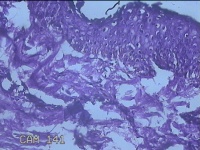

左眼外侧缘上肿物

性别

女

年龄

60岁

临床诊断

痣;疣

左眼上睑缘白色丘疹1年余。

灰白粉红色肿物0.8x0.3x0.2cm两个,表面光滑。

图1